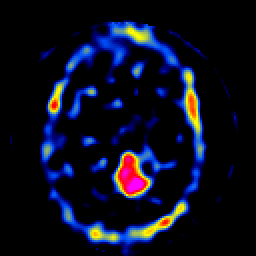

SPECT TL Study #8 -- Slice #32

[Home][Help][Clinical][Tour 1][Tour 2][Tour 3] Slice 32